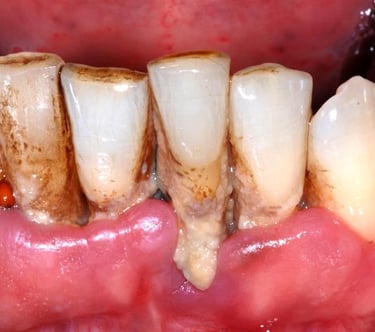

Gum disease treatment may be nonsurgical or surgical, depending on the stage of disease and your oral and overall health. Nonsurgical treatments include scaling and root planing and antibiotics. Surgical options include pocket reduction surgery and guided tissue regeneration

What is gum disease treatment?

Gum disease occurs when plaque and tartar build up on your teeth surfaces. Your gums react to the bacteria in these irritants and become red, swollen and tender. Your gums may also bleed when you brush or floss.

The sooner you treat gum disease, the better chance you have for long-lasting oral health. At its earliest stage (gingivitis), gum disease is reversible. But the later stages (periodontitis) damage your gums and underlying bone. This results in gaps — or periodontal pockets — around your teeth, leading to further infection, loose teeth and even tooth loss.

Dental prophylaxis

Dental prophylaxis is a routine dental cleaning — like the one that many people have with their hygienist twice a year. During this procedure, a provider removes plaque and tartar from your teeth surfaces.

Surgical gum disease treatments

Removing the tartar buildup and clean your root surfaces. Smooth and reshape areas of damaged bone, making it harder for bacteria to hide and grow. Finally, we reposition your gums and suture them into place.